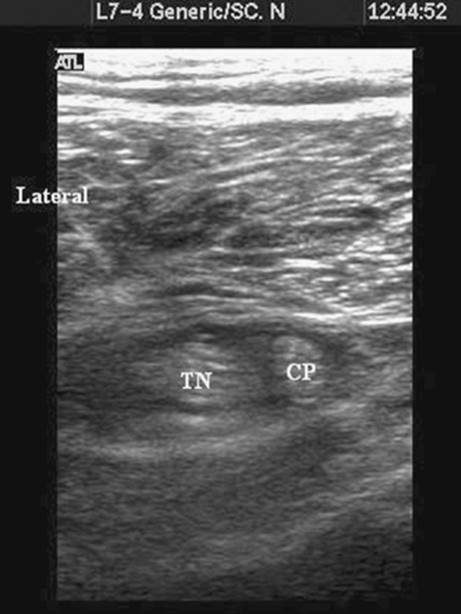

Once the needle tip lies adjacent to the nerve a muscle contraction can be elicited if preferred by slowly increasing nerve stimulator current until a twitch is seen (commonly less than 0.5 mA). Once nerve identity is confirmed, local anesthetic is incrementally injected. It is important to examine the spread of local anesthetic and ensure that spread is seen encircling the nerve (Fig. 41-5). Several needle positions may be needed to ensure adequate spread on either side of the nerve. The nerve can often be seen more easily to split into tibial and common peroneal components after injection (Fig. 41-6). The often-inadequate spread on injection with the needle in a fixed position may explain why many popliteal blocks with apparently excellent nerve stimulator endpoints fail even with large volumes of local anesthetic.

Figure 41-6. Local anesthetic (dark area) seen encircling the two tibial and common peroneal nerves below the division of the sciatic nerve. TN, tibial nerve; CP, common peroneal.